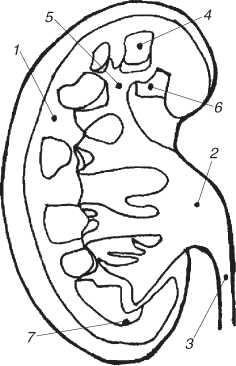

Внутреннее строение почки

1 – корковый слой почки;2 – почечная лоханка; 3 – мочеточник; 4 – почечная пирамида, оканчивающаяся сосочком; 5 – большая почечная чашка; 6 – малая почечная чашка; 7 – мозговой слой почки